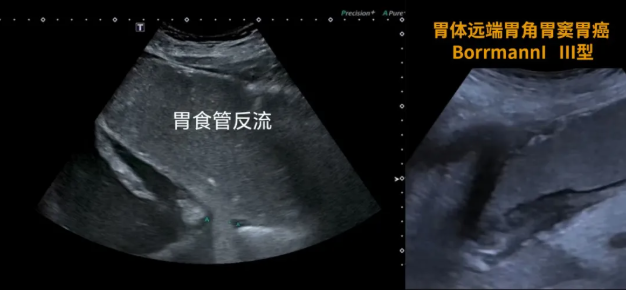

1.胃肠道肿瘤性病变;

2.胃肠道炎症、溃疡;

3.粘膜病变,如胃黏膜脱垂症、胃巨皱褶症等;